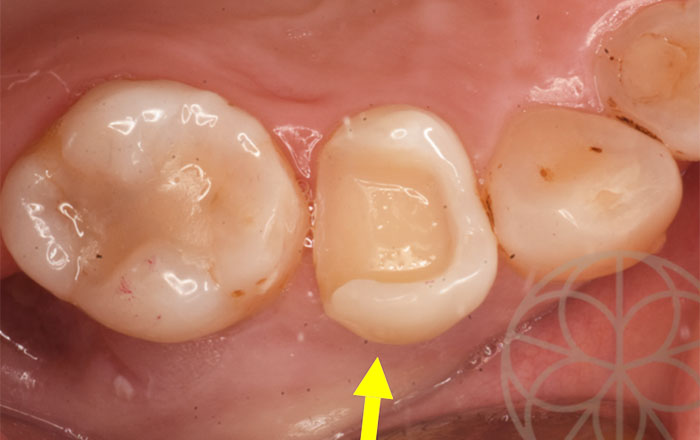

治療前

治療前状況

過去に銀歯で治した患者様。

当院メインテナンス中に、異常がわかり、早めに処置をすることができました。メインテナンスに来ていなければ発見が遅れていたかもしれません。

以前に他院で装着した銀のインレーがカリエスの再発をおこし、銀を外して、みると再発した部位がわかります。